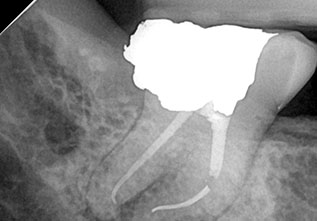

This dental procedure code, refers to a type of X-ray known as periapical. This term is used because these X-rays capture the entire tooth all the way down to the tissues at the tip of the tooth root – an area referred to as the periapical area.

A periapical X-ray will show one or two teeth in their entirety in one single image, right from the crown of the tooth which is the part exposed in the mouth to the very tips of the tooth roots located in the jawbone, as well as the surrounding bone supporting this tooth.